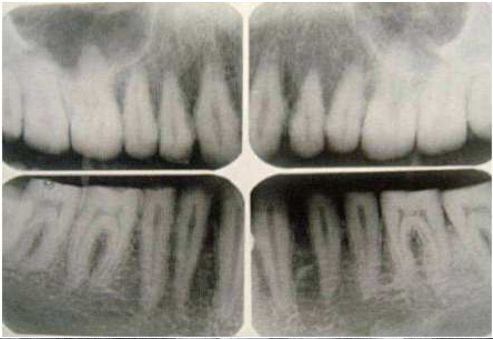

55.如全口環狀X光片所示,下顎骨左側可以發現多房性(multilocular) 放射線透光性病灶,並呈現有多顆牙齒之 牙根吸收,下列何者是較為可能之診斷? (A)鈣化齒源囊腫(calcified odontogenic cyst) (B) 含齒囊腫(dentigerous cyst) (C)齒源性角化囊腫(odontogenic keratocyst) (D)始基囊腫(primordial cyst)